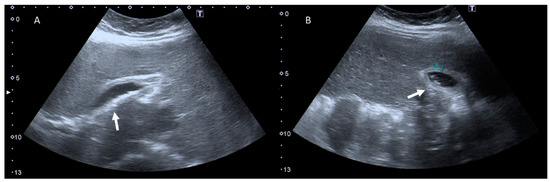

In modern clinical practice, there is an increasing dependence on imaging techniques in several settings, and especially during emergencies. Consequently, there has been an increase in the frequency of imaging examinations and thus also an increased risk of radiation exposure. In this context, a critical phase is a woman’s pregnancy management that requires a proper diagnostic assessment to reduce radiation risk to the fetus and mother. The risk is greatest during the first phases of pregnancy at the time of organogenesis. Therefore, the principles of radiation protection should guide the multidisciplinary team. Although diagnostic tools that do not employ ionizing radiation, such as ultrasound (US) and magnetic resonance imaging (MRI) should be preferred, in several settings as polytrauma, computed tomography (CT) nonetheless remains the examination to perform, beyond the fetus risk. In addition, protocol optimization, using dose-limiting protocols and avoiding multiple acquisitions, is a critical point that makes it possible to reduce risks. The purpose of this review is to provide a critical evaluation of emergency conditions, e.g., abdominal pain and trauma, considering the different diagnostic tools that should be used as study protocols in order to control the dose to the pregnant woman and fetus. Full article

Show Figures

Figure 1